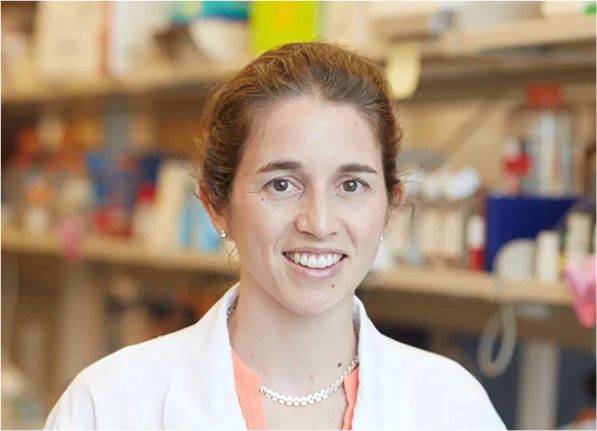

了解研究人员和患者的故事,

看他们如何向癌症发起挑战

了解研究人员和患者的故事,

看他们如何向癌症发起挑战